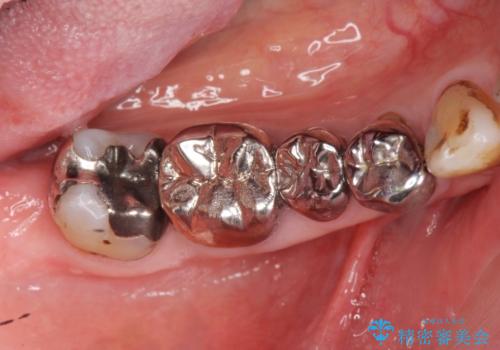

大臼歯 再根管治療

- 銀歯を白くしたいとの希望で来院されました。

せっかく銀歯を白くしても後々根管治療が必要になり、また壊して再治療を行うことを避けたいとの事でしたので、再根管治療から行っていきます。

ただ銀歯を白くするのではなく長期的な予後には歯の内部、根管治療の成功が必要不可欠です。